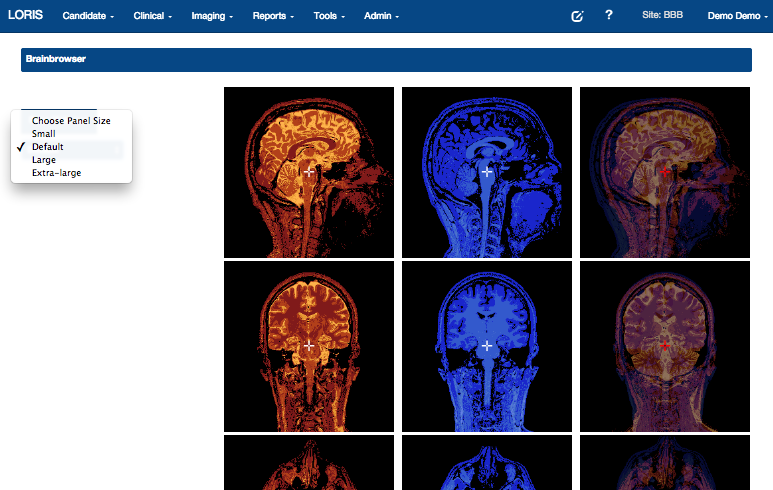

BrainBrowser

..a set of web-based 3D visualization tools primarily used for viewing neurological data i.e. MRI scans.

It allows for real-time manipulation and analysis of 3D neuroimaging data through any modern web browser. TRY ME!

BrainBrowser - 3D Surface Viewer